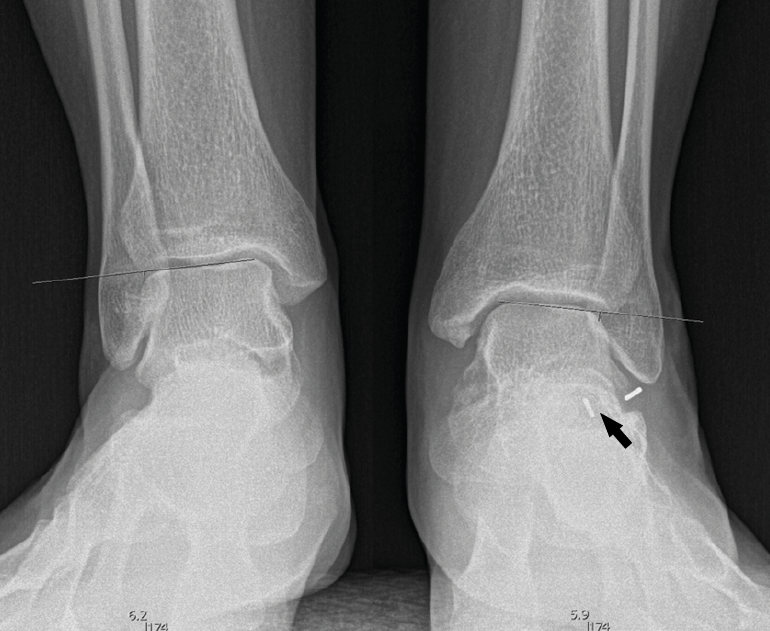

Figura 10. Tras la cirugía: primer caso a la izquierda, segundo caso a la derecha. Las flechas señalan el pie intervenido.

A los 6 meses (Figura 10), la evolución es correcta, con corrección clínica y radiológica del plano/valgo y manteniendo cierta movilidad de la articulación subtalar (15°).

En el primer caso (Figura 11), presenta el siguiente balance articular: flexión = 45°; extensión = 15°; inversión = 10°; eversión = 5°. Valgo talar de 10°. Refiere molestias discretas en el seno del tarso a la hiperextensión. Marcha correcta. Escala AOFAS del tobillo: 82 (30-42-10) . Los ángulos radiológicos finales son: Moreau-Costa-Bartani interno = 134°; declinación talar = 18,3°; Meary = 1,6°; Kite = 16,2°; taloescafoideo= 63,3°.

Figura 11. Radiografía del segundo caso poscirugía: corrección del pie plano y visualización de la endortesis (flecha) en el seno del tarso.

En el segundo caso (Figura 12), presenta un balance articular: flexión = 45°; extensión = 20°; inversión = 10°; eversión = 5°. Valgo del talón de 9°. La paciente refiere alguna molestia sin definir en el retropié y realiza una marcha correcta. Escala AOFAS del tobillo: 84 (30-44-10). Los ángulos radiológicos finales son: Moreau-Costa-Bartani interno = 131°; declinación talar = 13,8°; Meary = 1,1°; Kite = 15,1°; taloescafoideo = 77,4°.

Figura 12. Radiografía de perfil de ambos pies del segundo caso. Flecha en la endortesis del pie intervenido.